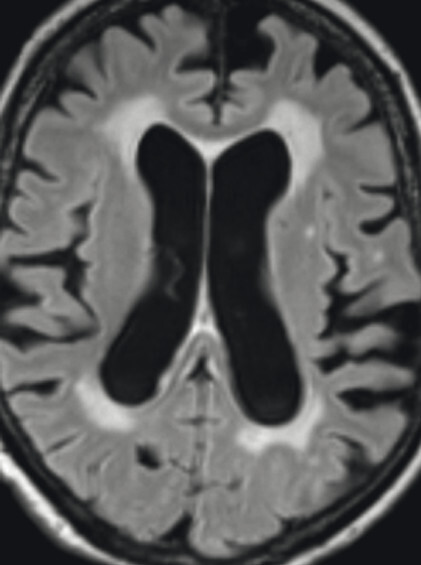

Abb. 69.10 Parkinson-Syndrome: Differenzialdiagnose progressive supranukleäre Parese mit Parkinson-Syndrom.

74-jähriger Patient mit linksbetontem Parkinson-Syndrom und aktuell deutlicher demenzieller Entwicklung mit exekutiver Störung und Zeitgitterstörung. In der T1w 3-D-MRT zeigt sich ein unauffälliges Mesenzephalon (a) mit einer normalen Midbrain/Pons-Ratio von 0,61 (kurzer Durchmesser des Mesenzephalons: 9,9 mm; kurzer Durchmesser des Pons: 16,1 mm, beide durch eine rote Linie dargestellt; b). Die automatisierte Ganzhirnvolumetrie (c) lässt außerdem ein anomales Hirnvolumen frontal bis parietal beidseits erkennen. In der 2 mm dünnen transversalen SWI-Schicht findet sich kein Schwalbenschwanzzeichen (d).

a T1w 3-D-MRT-Sequenz.

b T1w 3-D-MRT-Sequenz mit eingezeichneten Durchmessern.

c Ganzhirnvolumetrie.

d Transversale SWI.